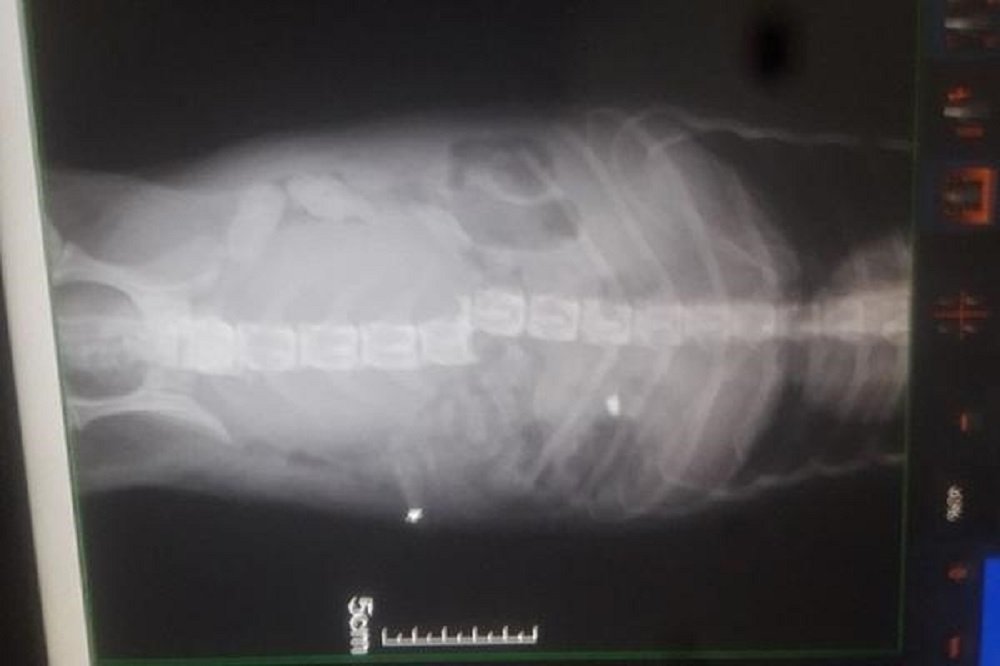

Раненного пёсика по кличке Кузя отвезли в реабилитационный центр «Святобор» в городе Шахты. Ветеринары выяснили, что в собаку стреляли из пневматического оружия. Пуля раздробила позвоночник, об этом сообщает donday.ru.

Рентген показал, что восстановить позвоночник песику не получится. Несколько дней собачку кололи дорогим обезболивающим, деньги на которые собрали неравнодушные горожане.